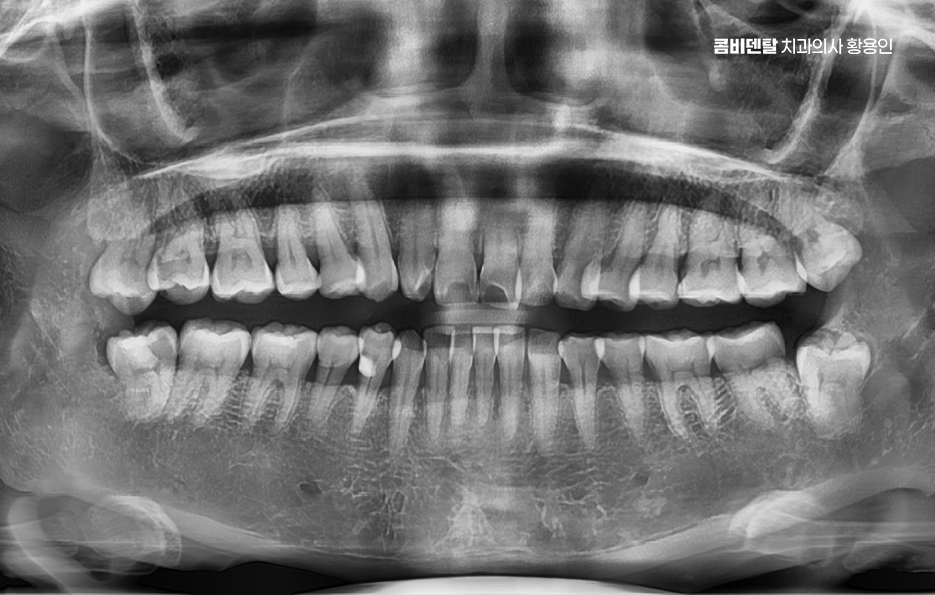

사랑니는 보통 10대 후반에서 20대 초반 사이에 나기 시작하는 어금니 맨 끝쪽의 치아로 사람마다 나는 시기도 다르고, 아예 나지 않는 경우도 있고, 똑바로 나지 않고 누워서 나거나 비스듬히 나는 경우도 있었어요.

특히 아래쪽 사랑니는 공간이 부족한 경우가 많아서 정상적으로 나기보다는 매복되거나 비뚤게 나는 경우가 많아서 문제가 생기기 쉽고, 결국 문제가 심해지다가 발치를 안하기 어려운 단계로 이어지는 경우가 많이 있어요

아래 사랑니에서 문제가 생기는 대표적인 원인은 공간 부족으로 사랑니가 나올 무렵에는 앞선 치아들이 이미 자리 잡고 있기 때문에 사랑니가 나올 자리가 부족한 경우가 대부분이어서 사랑니가 잇몸 속에서 옆으로 누워서 자라거나, 부분적으로만 머리를 내밀고 자라는 일이 많다보니 이런 상태에서는 칫솔이 닿지 않아서 음식물이 끼기 쉽고, 세균이 쌓이면서 염증이 생기기 쉬운 거예요.

사랑니가 제대로 나지 않으면 그 앞에 있는 어금니에도 영향을 줄 수 있는데 사랑니가 비스듬히 눌러주는 방향으로 자라면 그 앞 치아 뿌리에 압박이 생기고, 치아 사이에 음식물이 자주 끼게 되면서 충치가 생기거나 잇몸 염증이 퍼지게 되는 것이며 앞 치아에 생긴 충치는 인접면 충치인 경우가 많기 때문에 일반 충치보다 더 치료가 어렵고, 경우에 따라서는 신경치료 까지 이어질 수도 있었어요.

그 이유는 아래턱 뼈가 위턱보다 단단하고 밀도가 높아서 치아가 쉽게 안 빠지고, 하치조 신경도 가까이 있기 때문이고 매복된 사랑니일수록 치료가 까다로워질 수 있다는 점에서 사랑니 발치 경험이 많은 치과의사를 잘 만나는 것도 중요한 거예요